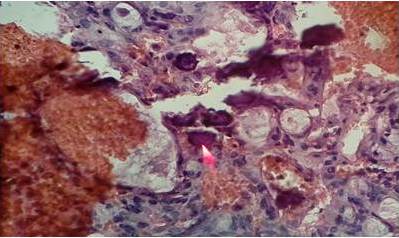

Paciente de 61 años de edad IVG IIIP IC quien en mayo de 2005 presentó aumento de volumen abdominal y dolor en fosa iliaca derecha por lo cual acude a facultativo quien realiza ecosonograma abdominal evidenciando tumor ecomixto de ovario derecho, es llevada a mesa operatoria donde realizan ooforectomía derecha, cuya biopsia definitiva reportó cistoadenocarcinoma papilar mucinoso, moderadamente diferenciado, es referida al Servicio Oncológico Hospitalario del IVSS en junio de 2005 donde se evalúa, se solicitan estudios de extensión y se decide en reunión de servicio realizar cirugía estadiadora de ovario. La biopsia definitiva correspondiente a útero, ovario izquierdo, muestras peritoneales, epiplón y apéndice cecal reportaron negativas para malignidad por lo que se concluye con el diagnóstico de, adenocarcinoma papilar mucinoso de ovario estadio IA, se mantiene en control anual y en diciembre 2017 paciente refiere trastornos del hábito evacuatorio, y dolor pélvico. Al examen físico abdomen blando depresible no doloroso a la palpación. Genitales externos normo configurados, especuloscopia se evidencia en cúpula vaginal lesión de aproximadamente 3 cm friable indurada, sangrante. Al tacto vaginal se palpa paredes vaginales lisas, se palpa tumoración indurada de aproximadamente 3 cm en pared posterior y 1/3 superior de vagina, de bordes lisos. Tacto rectal, se palpa tumoración de aproximadamente a 6 cm de margen anal indurada, de bodes lisos que comprime y desplaza la pared anterior de recto, ocluyendo la luz del mismo en un 40 %. Se solicitan estudios de endoscopia inferior sin alteraciones. Se solicitan marcadores tumorales con elevación del Ca 125 en 171 U/mL. Tomografía abdomino-pélvica se aprecia lesión a nivel de cúpula vaginal de aproximadamente 6 cm hiperdensa de bordes regulares que comprime recto. Citología de abril 2018 reporta positivo para malignidad, adenocarcinoma, Biopsia de cúpula vaginal, adenocarcinoma de patrón mixto sero mucinoso (mucinoso 80 % y seroso 20%), presencia de calcificaciones tipo psammomatoso, material fibrinoide abundante, invasión vascular no observada. Es discutida en reunión de servicio y se concluye que paciente no tiene criterios de resecabilidad y se refiere para iniciar tratamiento por el servicio de oncología médica. Se indican controles estrictos cada tres meses por el servicio de ginecología oncológica.